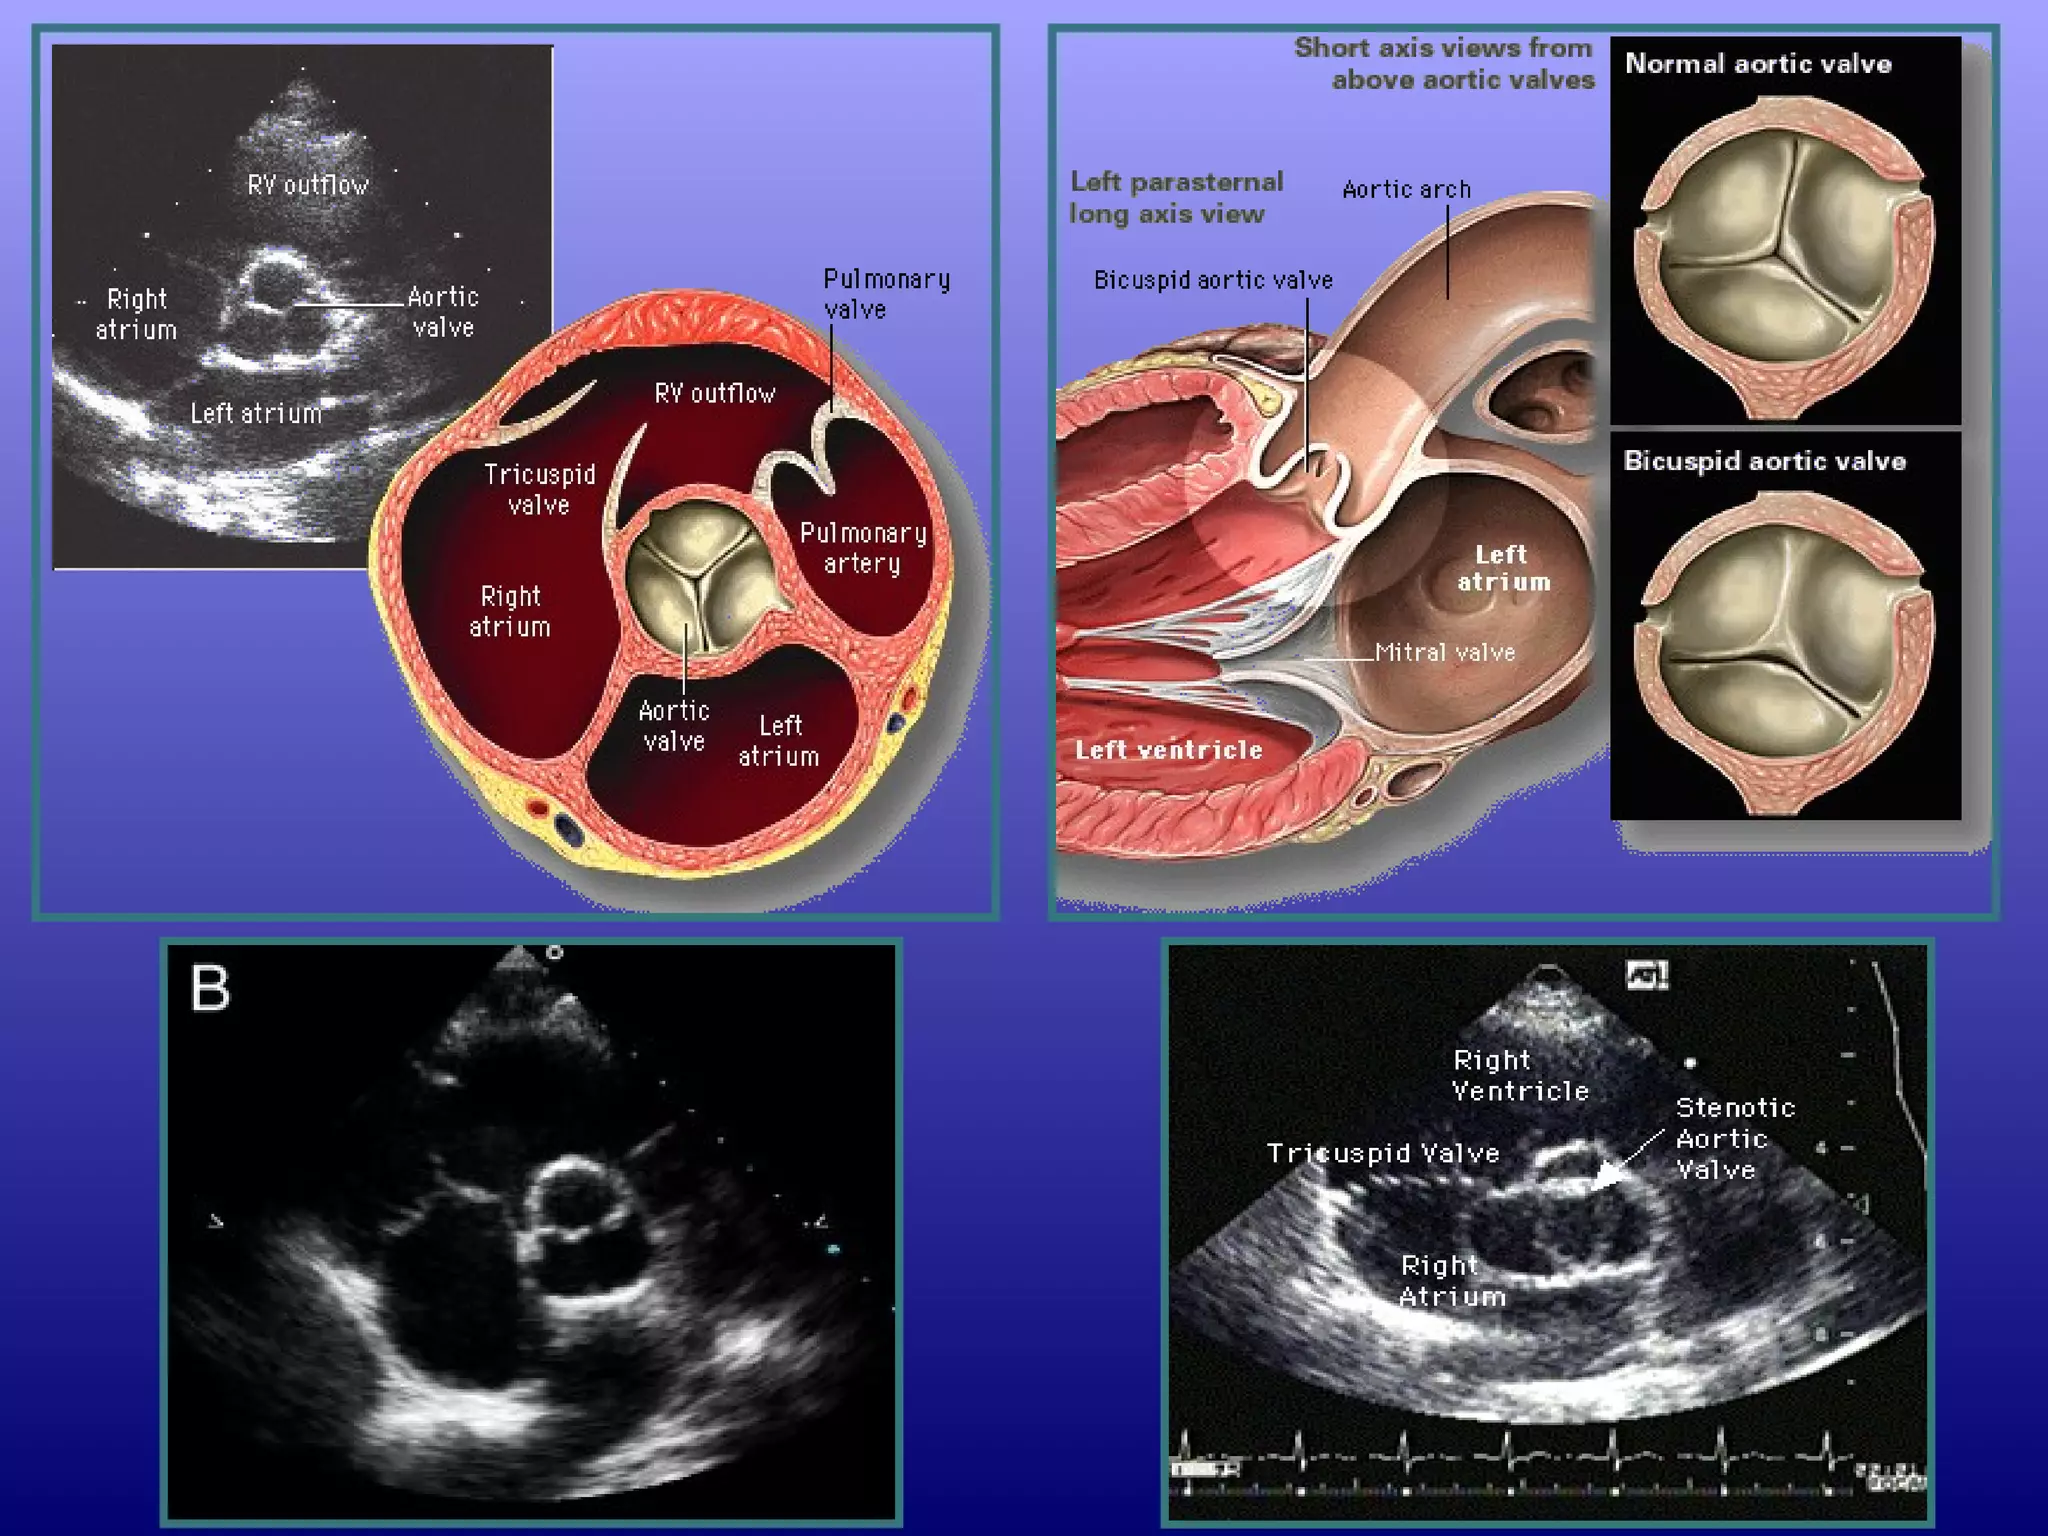

At the basal (aortic valve) level, the right atrium, septal

and anterior leaflets of the tricuspid valve, right

ventricular free wall, right ventricular outflow tract,

pulmonic valve, main pulmonary artery, and left

atrium can be seen "surrounding" the centrally

oriented aortic valve.

All three leaflets of the aortic valve may be identified,

forming a "Y" configuration during ventricular

diastole and "upside-down triangle" during

ventricular systole

At the basal(aortic valve) level, the right atrium, septal and anterior leaflets of the tricuspid valve, right ventricular free wall, right ventricular outflow tract, pulmonic valve, main pulmonary artery, and left atrium can be seen "surrounding" the centrally oriented aortic valve. All three leaflets of the aortic valve may be identified, forming a "Y" configuration during ventricular diastole and "upside-down triangle" during ventricular systole